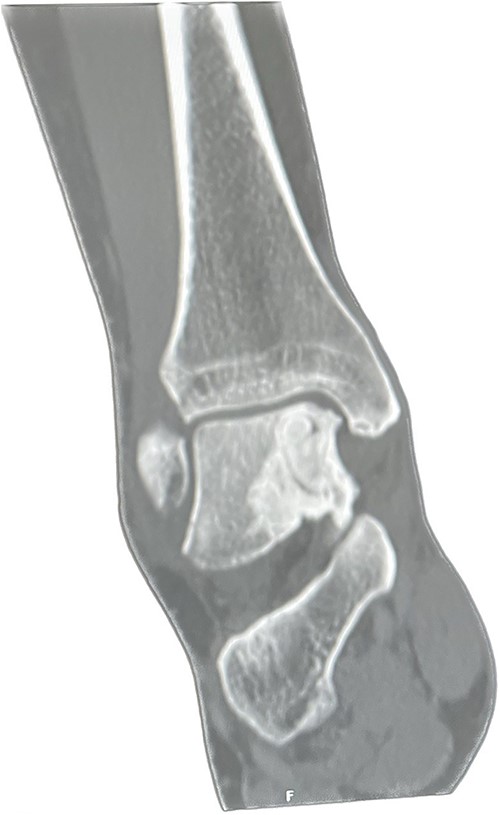

He presented with no relevant medical history and worked as a chemical plant supervisor, which required continuous movement throughout the day. Clinical examination revealed deep-seated pain around the medial aspect of the ankle with an intact range of motion and ankle alignment. His MOXFQ score was 48/80. CT scan revealed a large but well-contained, subchondral cyst in the medial talus of the ankle (Fig. 4).